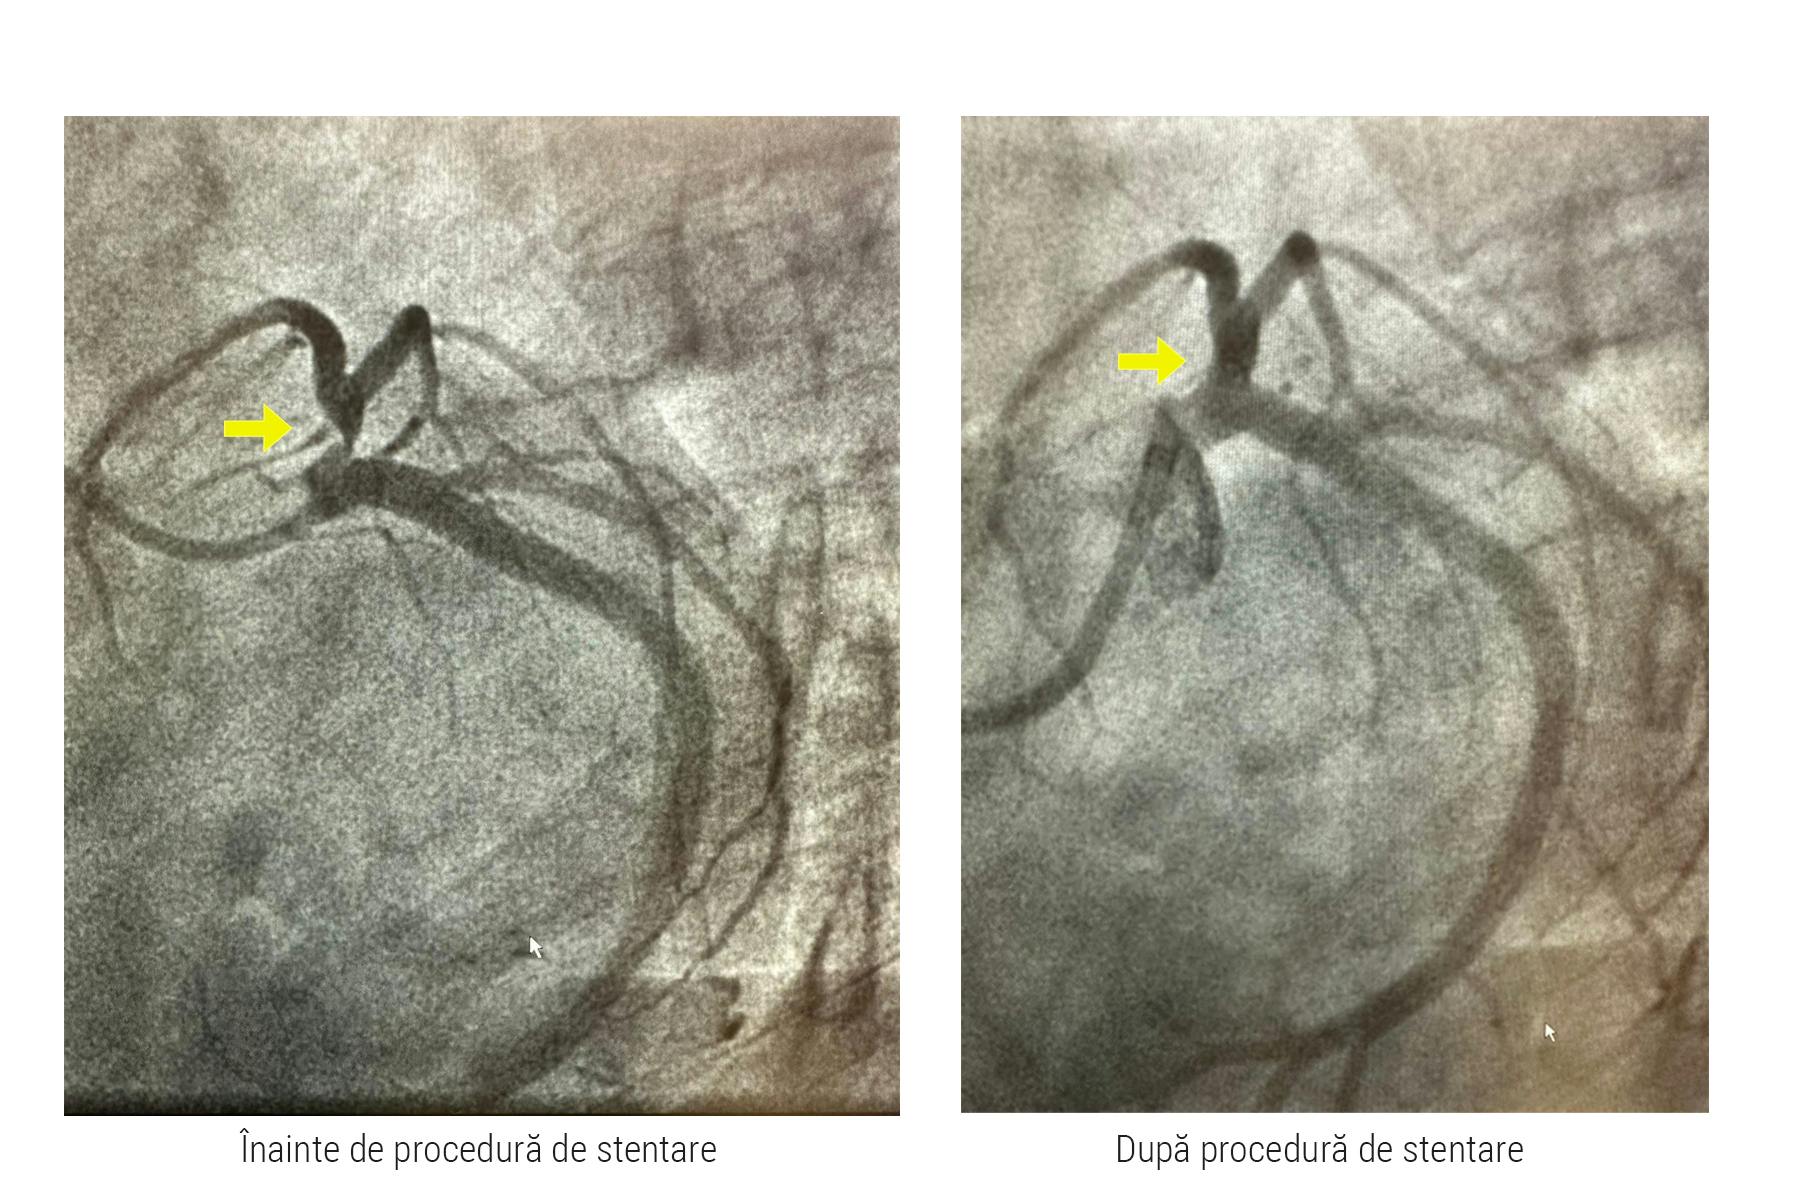

Coronarografia este cea mai utilă și cea mai rapidă investigație care identifică zona unde vasul de sânge este blocat. În cazul pacientei noastre, după identificarea blocajului, doctorul Adnan Mustafa a efectuat implantarea de stent, procedură ce poartă denumirea de angioplastie coronariană cu stent. Practic, în dreptul blocajului, medicul a folosit un cateter predispus în capăt cu un mic balonaș și stent pentru a împinge și aplatiza grăsimea acumulată în arteră. Prin această manevră medicală executată în interiorul arterei, medicul interventionist redă circulația normală a sângelui, iar pentru a se asigura că acest flux nu va mai fi întrerupt, va monta un mic dispozitiv denumit stent.